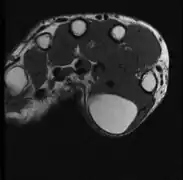

A physical exam is typically the easiest way to diagnose it. Rarely, a tissue biopsy or imaging may be required. The imaging modality of choice is magnetic resonance imaging (MRI) because it has superior sensitivity of distinguishing it from liposarcoma as well as mapping the surrounding anatomy.[22]

MRI showing lipoma of the arm

MRI showing lipoma of the arm -